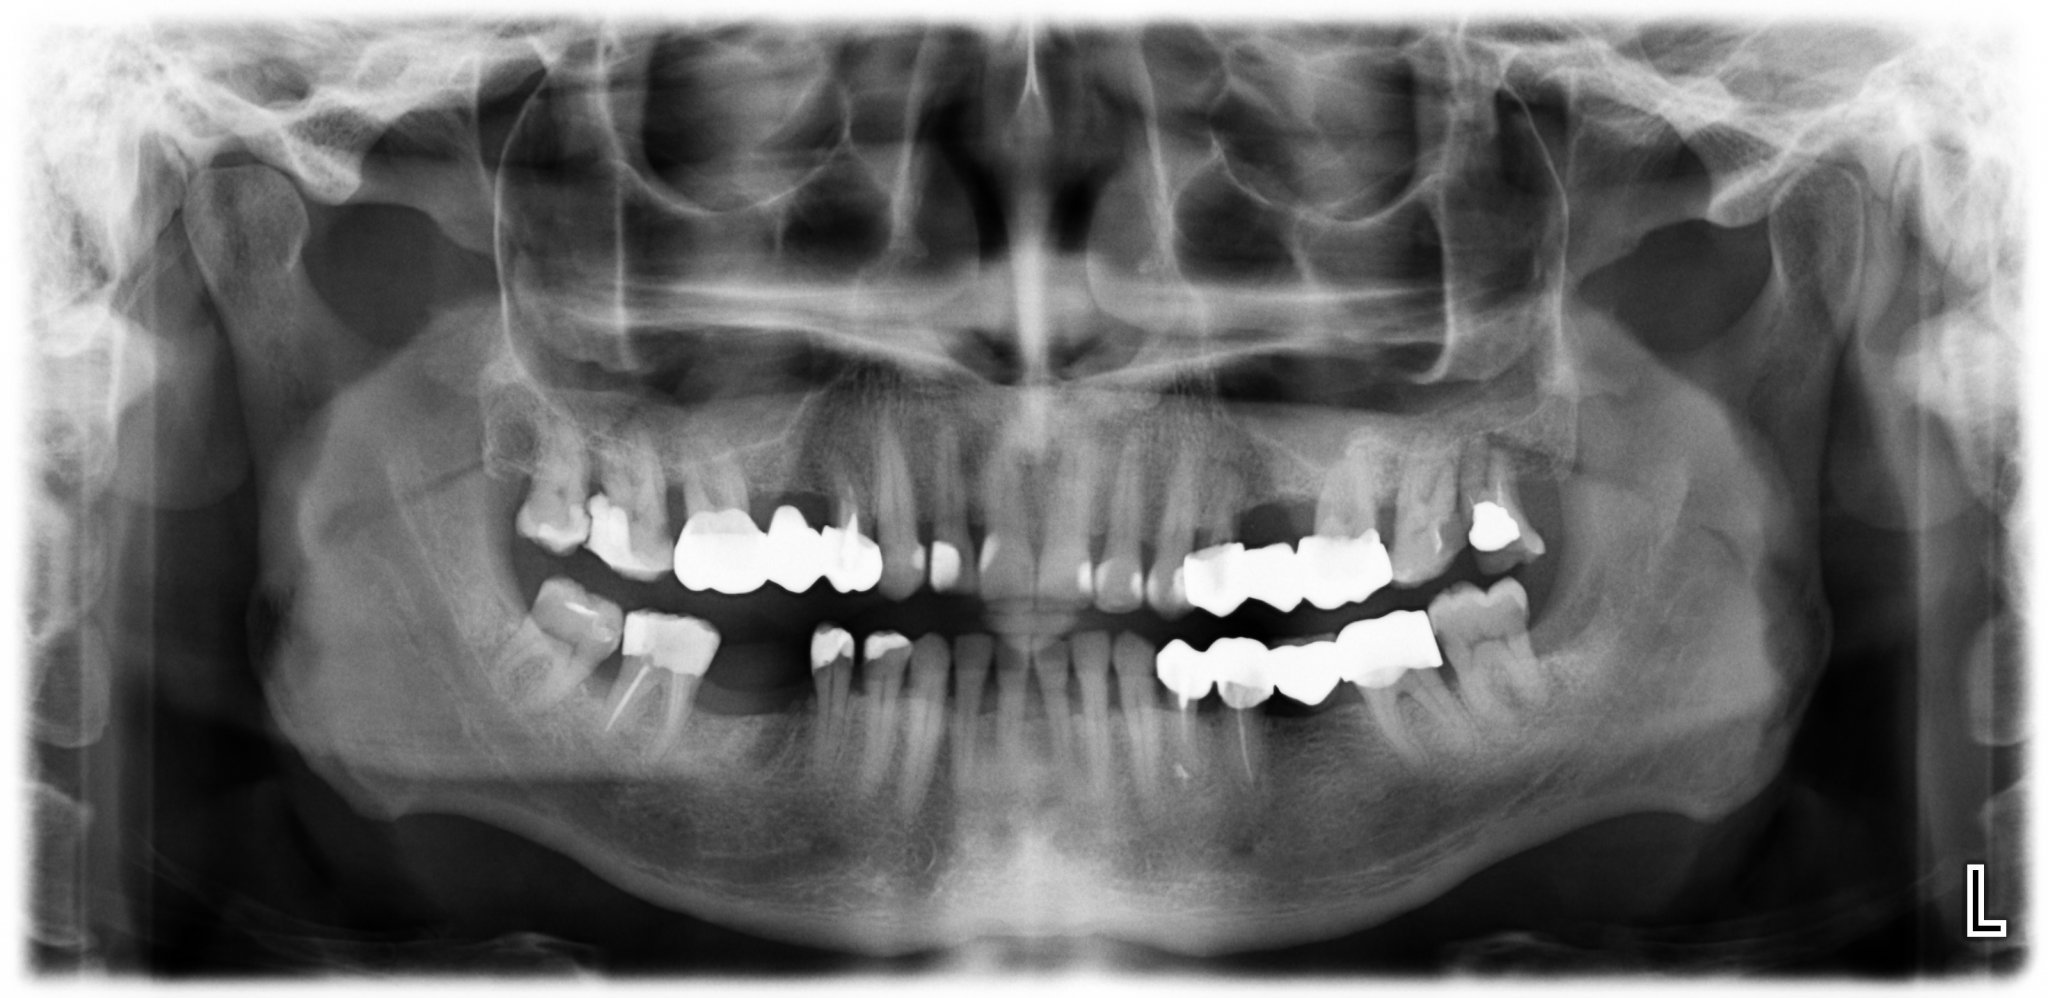

Кое е по-добро - импланти или мостове?

Имплантите и мостовете имат своите предимства и недостатъци. Имплантите често се рекламират, но не винаги са успешни в дългосрочен план. Те изискват определени условия на организма, които могат да увеличат шансовете за успешно интегриране в костта. Освен това поставянето на имплант може да бъде по-скъпо и не гарантира по-голям процент на успеваемост. Мостовете, от друга страна, могат да бъдат поставени по-бързо и по-евтино, но изискват изпиляване на съседните зъби. Всеки случай трябва да бъде оценен индивидуално от имплантолог, който може да предложи най-подходящото решение за конкретния случай.